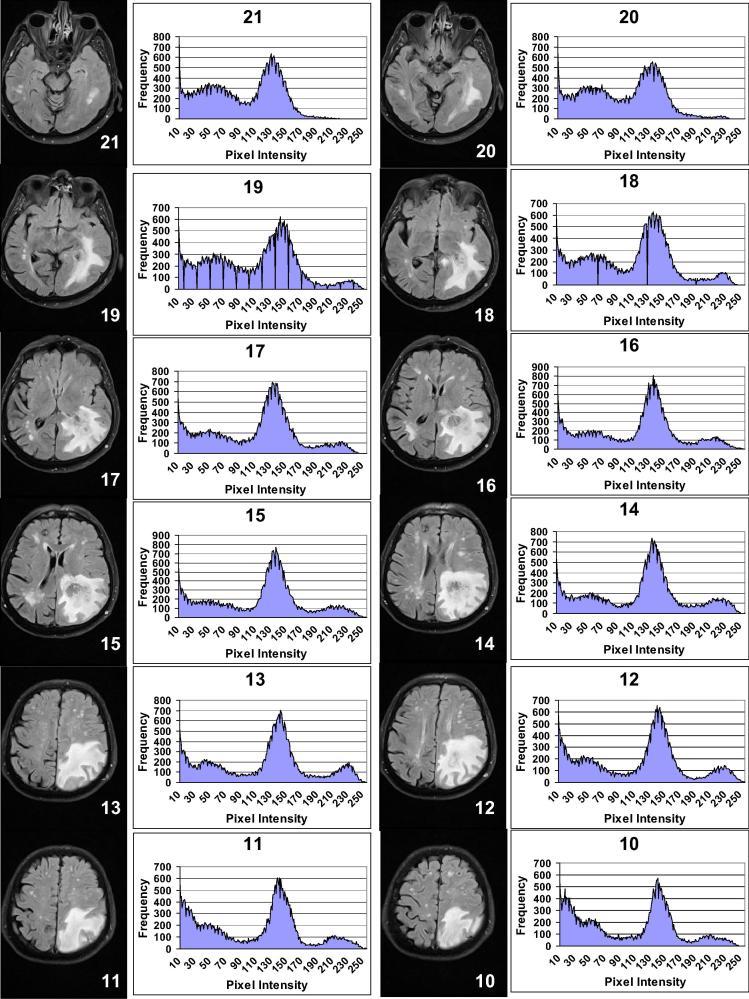

This research presents signal-image post-processing techniques called Intensity-Curvature Measurement Approaches with application to the diagnosis of human brain tumors detected through Magnetic Resonance Imaging (MRI). Post-processing of the MRI of the human brain encompasses the following model functions: (i) bivariate cubic polynomial, (ii) bivariate cubic Lagrange polynomial, (iii) monovariate sinc, and (iv) bivariate linear. The following Intensity-Curvature Measurement Approaches were used: (i) classic-curvature, (ii) signal resilient to interpolation, (iii) intensity-curvature measure and (iv) intensity-curvature functional. The results revealed that the classic-curvature, the signal resilient to interpolation and the intensity-curvature functional are able to add additional information useful to the diagnosis carried out with MRI. The contribution to the MRI diagnosis of our study are: (i) the enhanced gray level scale of the tumor mass and the well-behaved representation of the tumor provided through the signal resilient to interpolation, and (ii) the visually perceptible third dimension perpendicular to the image plane provided through the classic-curvature and the intensity-curvature functional.